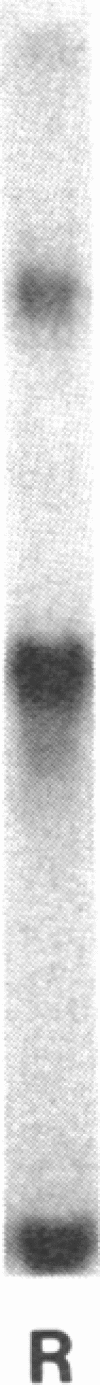

Factor VIII antigen (VIII:CAg) exhibits molecular weight heterogeneity in normal plasma. We have compared the relative quantities of VIII:CAg forms present in normal individuals (n = 22) with VIII:CAg forms in renal dysfunction patients (n = 19) and in patients with disseminated intravascular coagulation (DIC; n = 7). In normal plasma, the predominant VIII: CAg form, detectable by sodium dodecyl sulfate polyacrylamide gel electrophoresis, was of molecular weight 2.4 X 10(5), with minor forms ranging from 8 X 10(4) to 2.6 X 10(5) D. A high proportion of VIII:CAg in renal dysfunction patients, in contrast, was of 1 X 10(5) mol wt. The patients' high 1 X 10(5) mol wt VIII: CAg level correlated with increased concentrations of serum creatinine, F1+2 (a polypeptide released upon prothrombin activation), and with von Willebrand factor. Despite the high proportion of the 1 X 10(5) mol wt VIII:CAg form, which suggests VIII:CAg proteolysis, the ratio of Factor VIII coagulant activity to total VIII:CAg concentration was normal in renal dysfunction patients. These results could be simulated in vitro by thrombin treatment of normal plasma, which yielded similar VIII:CAg gel patterns and Factor VIII coagulant activity to antigen ratios. DIC patients with high F1+2 levels but no evidence of renal dysfunction had an VIII:CAg gel pattern distinct from renal dysfunction patients. DIC patients had elevated concentrations of both the 1 X 10(5) and 8 X 10(4) mol wt VIII:CAg forms. We conclude that an increase in a particular VIII:CAg form correlates with the severity of renal dysfunction. The antigen abnormality may be the result of VIII:CAg proteolysis by a thrombinlike enzyme and/or prolonged retention of proteolyzed VIII:CAg fragments.